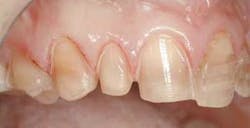

With our patient, this evaluation reveals the centrals to be approximately 8.5 mm wide and 9.5 mm long. (Fig. 3) This would make the existing W/L ratio 89 percent. The Golden Proportion evaluation shows that the centrals appear too wide and we see too much of the canines.

For the most visually pleasing effect, the teeth should have a slight mesial axial inclination. The observation of our patient's teeth reveals inclinations that do not follow this rule (Fig. 4 – black lines are desired; yellow lines existing).